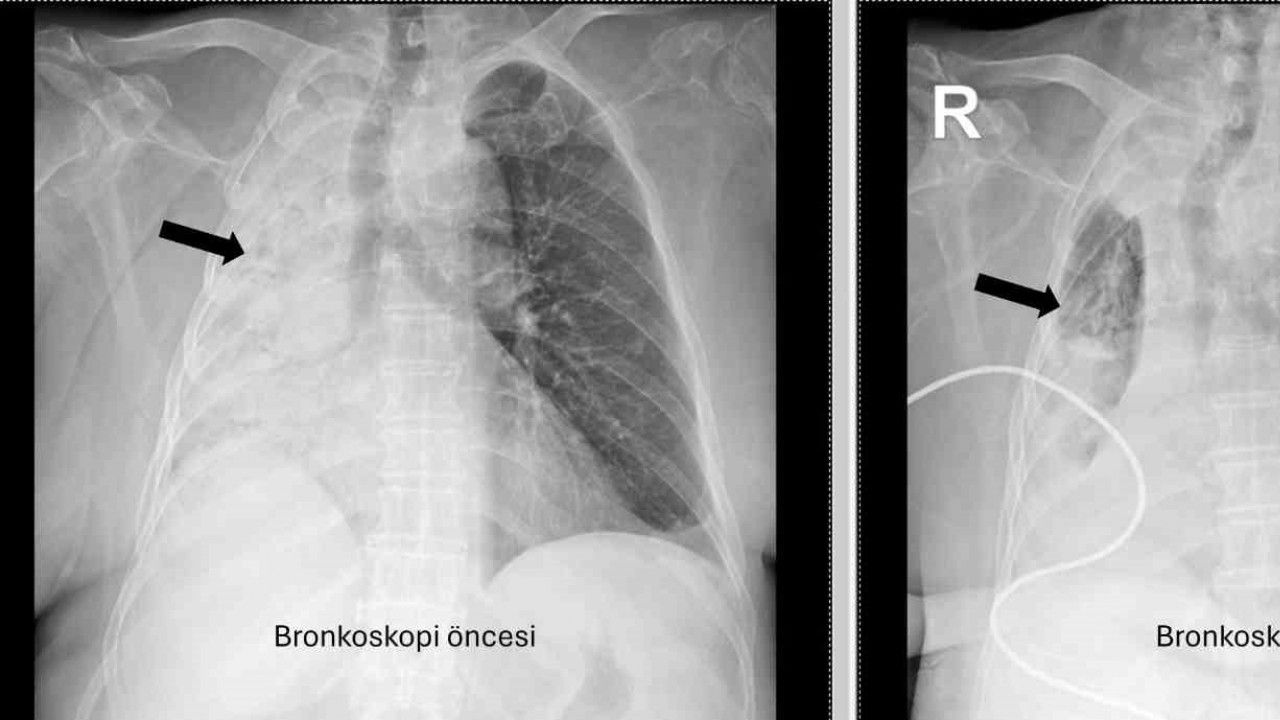

Denizli’de yaşayan ve emekli öğretmen olan 78 yaşındaki felçli kadın son zamanlarda sık sık akciğer enfeksiyonu nedeniyle hastaneye gidiyordu. 1 ay önce gittiği hastanede bronkoskopi yapılmasına rağmen sorun saptanmadığı öğrenildi. Yaşlı kadının son gittiği hastanede sağ akciğerinin tamamen kapandığının tespit edilmesi üzerine Pamukkale Üniversitesi Hastanesine başvuruldu. PAÜ Hastaneleri Göğüs Hastalıkları Anabilim Dalı Öğr. Üyesi Prof. Dr. Göksel Altınışık Ergur, tarafından yapılan tetkiklerde sağ akciğere giden hava yolunun bütünüyle kapalı olduğu görüldü. hastaya acil bronkoskopi planlanıp hemen işlemin gerçekleştirildiğini söyleyen Prof. Dr. Altınışık Ergur, "Fleksibl (esnek, eğilip bükülebilir) bronkoskop ile hava yolları incelenirken çok yoğun ve koyu sekresyon olduğu, bunun iyice temizlenmesi sonucunda ancak hava yollarının incelenebileceği görüldü. Aspiratör (içerideki salgıları emmeye yarayan bir cihaz) sayesinde hava yollarına steril sıvı verilip emilerek bu temizlik yapıldı. Sonrasında sağ akciğere giden hava yolunda sarı bir nesne olduğu görüldü. Bu hâliyle yabancı cisim olduğu anlaşıldığı gibi bunun mısır tanesine benzerliği de açıktı. Yabancı cismi çıkarma işlemi genel anestezi altında, rijit bronkoskop ile yapılmak üzere planlanabilirdi; çünkü bu durumun tedavisi yabancı cismin oradan, ek sorun oluşturmaksızın çıkarmaktı. Ancak, genel anestezi altındaki bir işlem için hastanın genel durumu bozuk olduğundan, özellikle ek hastalıkları ve enfeksiyon varlığı ile işlem riski artacağından hastadaki cismin fark edildiği sırada çıkarılmasına şans vermek daha uygun görüldü. Hava yolu içindeki sıvıları emen aspiratörün gücünü kullanılarak cismin çıkarılması mümkündü. Bronkoskobun ucu, sarı cismin gövdesine dayanıp aspiratör ile emme sayesinde ikisi birbirine sımsıkı yapıştırıldı. Emme gücünün azaltılmamasına dikkat ederek yabancı cisim ve bronkoskop, aynı zamanda hava yollarından dışarıya başarı ile çıkarıldı. İşlem sonrasında hasta yakınına mısır tanesi açısından tıbbi öykü yeniden sorulduğunda, hastamızın bundan beş ay önce yediği pizzanın üzerinde mısır taneleri olduğu öğrenildi. O sırada ani bir yakınma ortaya çıkmadığı için böyle bir ihtimal akla gelmemişti. Düşkün hastalar taneli gıdalar yerken, bu durumun fark edilmeden de gelişebileceğini göstermesi açısından önemli olan bu tablo, hastaların bir dedektif titizliği ile değerlendirilmesi gerekliliğini bir kez daha ortaya koymaktadır" dedi.